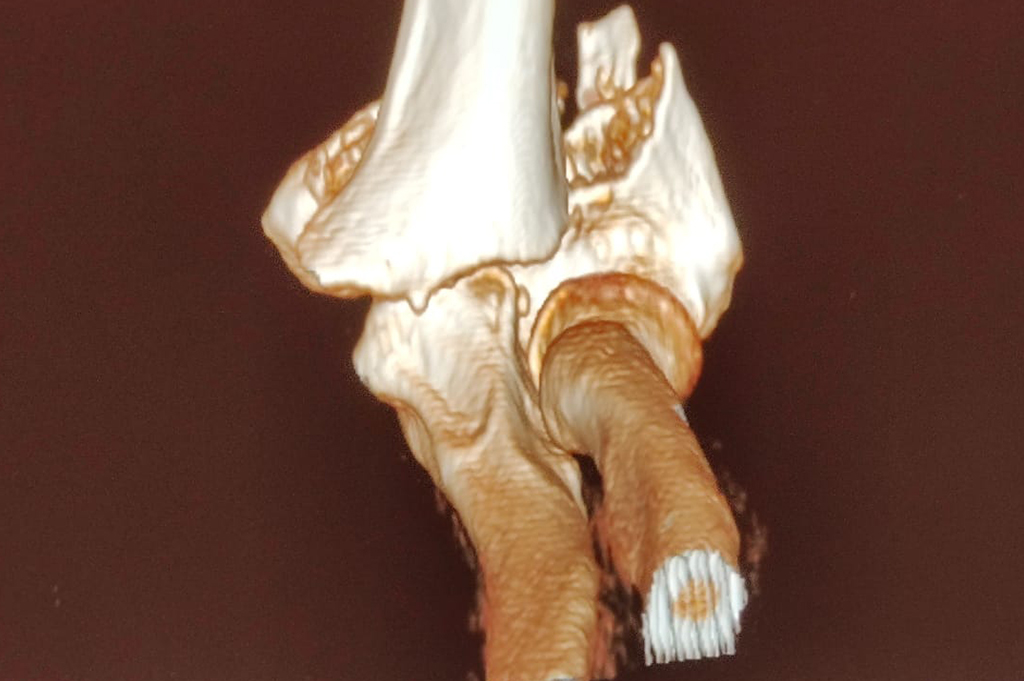

Distal Femur

Periprosthetic Fracture THR

Proximal Tibia